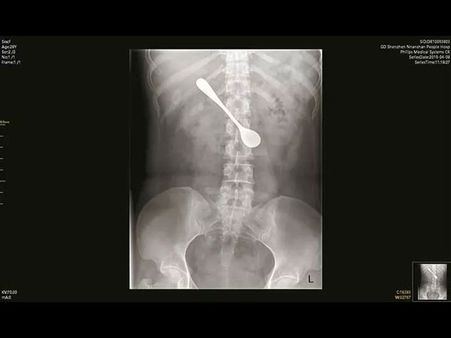

Woman Had A Spoon Stuck In Her Body

Several cases have been reported of unwanted items getting stuck in human bodies. These incidents are mostly accidental while some are intentional.

Here is one such case of a woman who had got a steel spoon stuck in her duodenum for days.

She claimed that she did not go to a doctor since she did not feel any pain! Check out more details of this bizarre case.

It is reported that the woman had used a 5 inches long steel spoon to dislodge a fish bone that had got stuck in her throat.

It is reported that the woman had the spoon lodged inside her body for at least four days long. During this phase she didn't experience any kind of pain or discomfort.

She visited the doctor after 4 days of the incident when she started feeling slight pain. The doctors decided to do a surgery on her by following the X-ray and an endoscopy procedure. The doctors were able to retrieve the spoon from the patient's duodenum.

Though the spoon was stuck in a complicated position, the doctors adjusted it before pulling it out. The entire process lasted for 10 minutes. Revealing about the details of the surgery, the doctors revealed that the metal object had caused some swelling and erosion in her duodenum.